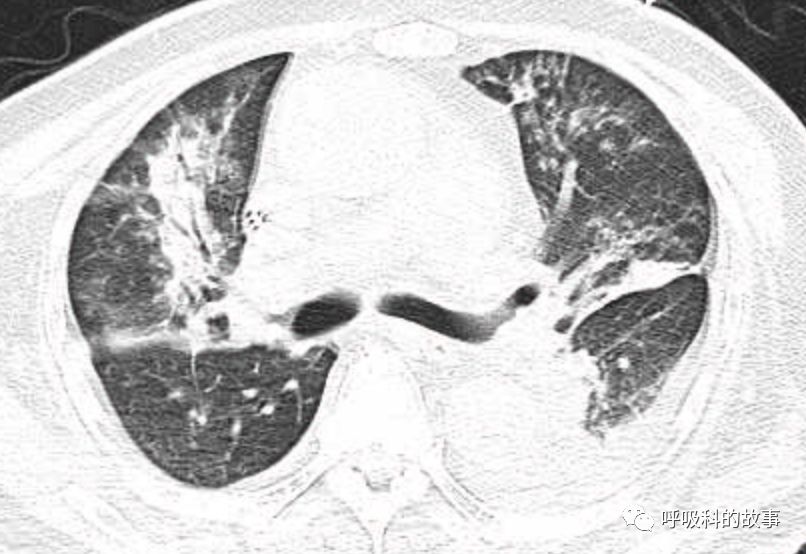

肺部CT如下:

以上的CT给我第一眼的感觉是肺炎,再结合患者有发热和血炎症指标明显增高,肺炎的诊断应该没有问题,但是胸水又是漏出液,结合脑钠肽增高和患者有胸闷气急的症状,心功能不全的诊断也能成立。在某些层面,肺部实变影以内中带为主,还要考虑肺水肿的诊断。入院后给予患者美罗培南抗感染、托拉塞米利尿治疗,以及化痰、雾化处理,患者体温在入院后三天就正常了,入院第五天复查NT-proBNP3390pg/ml;血常规示白细胞 13.5*10^9/L,中性粒细胞81.8%,淋巴细胞13.2%,超敏C-反应蛋白 25mg/L;电解质示钠 160mmol/L,氯 111mmol/L 。虽然炎症指标和心功能指标均有好转,但患者却仍旧精神差,每次查房时仍然表现嗜睡状,家属也反映患者不论白天还是夜晚多数时间不是太清醒。那么问题出在哪里呢?